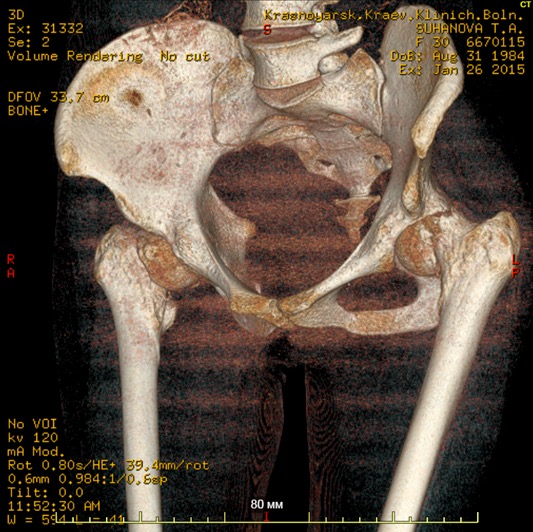

[Ortho] Патологические переломы шеек у пациентки 30 лет

Клинический случай, больная Т. 30 лет, 40 кг, анамнез: Считает себя

больной с начала декабря 2014 года, травмы отрицает, ни с чем не связывает.

Со слов на фоне полного здоровья появились отеки всего тела, после чего

боли в пояснице, правом к/с, затем т/б суставах. Обратилась за

мед.помощью по месту жительства, анемия до 40 г/л. Произведена

гемотрансфузия эр.взвесью, гемоглобин 100. При обследовании выявлена

киста яичника, с подозрением на злокачественный процесс с mts в кости

таза пациентка направлена на консультацию к онкологу. Злокачественный

процесс исключен.

Направлена на консультацию к гематологу , выполнена стернальная пункция.

Данных за миелому не получено. Больная в настоящее время проходит

дообследование с перспективой для паллиативного (а может и нет?)

протезирования т/б суставов. Из обследований: положительное RW, лечилась

10 лет назад. Гемоглобин 85, снижается, произведена гемотрансфузия до

100, формула б/о. Билирубин общ 47, прямой 9, по УЗИ, ФГС б/о.

Т-лимфоциты 60,Т - хелперы - 20. Остальное в пределах нормы, легкие

чистые. По МСКТ - дефект правой подвздошной. Как еще обследовать

больную? на что похоже? Спасибо заранее за ответы